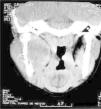

Radiográficamente existe una zona radiolúcida multilocular a nivel de la rama ascendente de la mandíbula (fig. 2) y en la tomografía axial computarizada (TAC) con expansión a tejidos blandos (fig. 3).